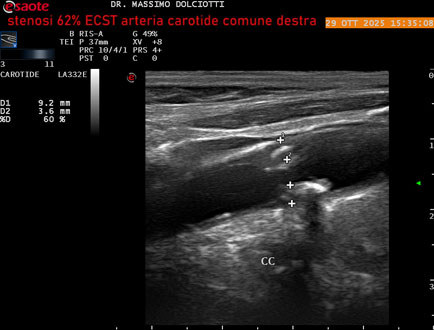

Data inserimento: 30/10/2025

Ecografia del: 29/10/2025

Strumento: Esaote MyLab Eight

Sonda: Lineare Multifrequenza 3-11 MHz

Età Paziente: F 75 anni

Motivazione dell'esame: controllo in pz con ateromasia carotidea ed ipercolesterolemia.

Commento all'esame: le immagini ed il video documentano all'arteria carotide comune destra placca disomogenea tipo 3 della classificazione di Gray Weale, che determina stenosi del 62% calcolato con metodo ECST.

Conclusioni: stenosi del 62% ECST dell'arteria carotide comune destra (62% ECST stenosis of the right common carotid artery).

Presentazione: Dr. Massimo Dolciotti - Ancona

Elaborazione digitale: Andrea Dini - Ancona